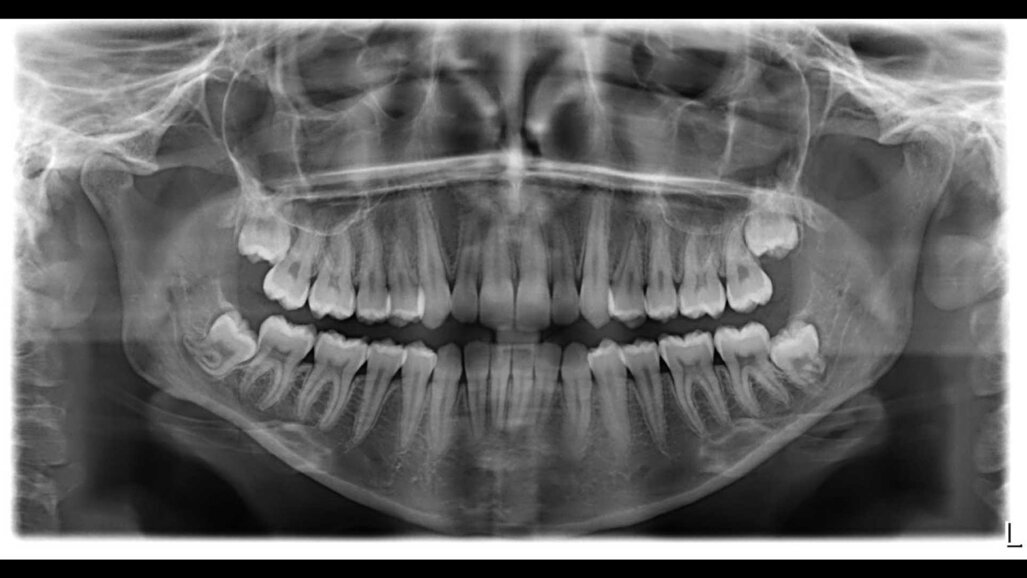

L’incisivo laterale di destra (1.2) si trova inoltre vestibolarizzato rispetto ai denti adiacenti e maggiormente intruso rispetto al controlaterale. In arcata inferiore, l’affollamento da canino a canino è di grado moderato. L’incisivo laterale di destra (4.2) è particolarmente lingualizzato rispetto ai denti adiacenti. È inoltre apprezzabile una classe I molare e canina bilaterale e contrazione dento-alveolare di entrambe le arcate. Si evidenziano accumuli di placca e tartaro specialmente in zona linguale a livello interprossimale. La paziente riferisce di aver eseguito l’igiene orale professionale più di 12 mesi prima. Dall’ortopanoramica iniziale tuttavia non si riscontrano segni di malattia parodontale, né riassorbimenti radicolari o risentimenti peri-apicali. Tutti i denti del giudizio sono presenti ma in inclusione ossea per mancanza di spazio in arcata.

Fig. 2 - Ortopantomografia a inizio trattamento.